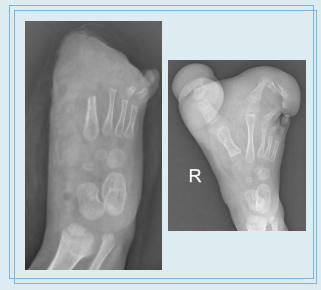

病例展示一:10月大的男孩,先天性右足巨趾

术前术后即刻大体

术前术后即刻X片

病例展示二:9岁男孩,先天性双足巨趾

外院术后2年复发,双足太大,无法正常穿鞋,来我院就诊

术前与术后3月大体照对比,家属对效果满意